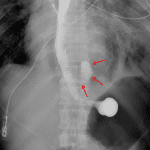

Findings

Chest radiograph

- Pneumomediastinum with gas tracking into the neck

- Moderate left and small right pleural effusions

- Patchy bibasilar opacities

Diagnosis

- Esophageal perforation (Boerhaave syndrome)

Large volume pneumomediastinum with paraesophageal fat stranding concerning for esophageal perforation (Boerhaave syndrome) in this patient with reported history of emesis. Recommend esophagram for further evaluation.

Small left pneumothorax.

Large left and moderate right pleural fluid collections with overlying airspace disease which is particularly concerning for aspiration in the setting of emesis.